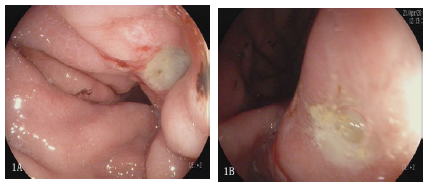

A 60-year-old male patient presented with intermittent upper abdominal pain for 6 months. The patient had no melena or weight loss. He received gastroscopy (EPK-i7000, Pentax, Japan) and there were multiple gastric ulcerations in the stomach (Figure 1). Furthermore, biopsy showed intramucosal lymphoid epithelial lesions (LEL) with HE is staining. Meanwhile, urea breath test showed strongly positive. Consequently, Immunohistopathology (IHC) showed diffused positive with CD20, CD79a (Figure 2A, 2B & 2C). Our experienced pathologist made the diagnosis of gastric DLBCL. Then the patient was admitted to Department of Hematology, PET-CT indicated that local gastric wall thickening. It was IEA stage based upon Lugano stage, the patient received Helicobacter Pylori eradication and CHOP chemotherapy (CTX 1.1+THP 75mg+VDS 4mg+PHD 90 mgd1-5). The patient underwent gastroscopy surveillance. Gastroscopy showed gastric scar and numerous inflammatory cells infiltration proved by biopsy after two months, three months, six months respectively (Figure 3A, 3B & 3C). Endoscopist performed gastroscopy ten months later after chemotherapy and we could find out a superficially depressed and reddish lesion (0- IIc) at the lesser curve of gastric body with white light imaging (WLI). The depressed lesion was approximately 0.8*1.0cm in size, and demarcate line was clear with chromoendoscopy (Figure 4A & 4B). Magnified endoscopy showed abnormal micro vessels and irregular micro surface pattern (Figure 4C). Biopsy showed some signet ring cells infiltration with atrophic gastritis (Figure 4D). The patient was transferred to Department of General Surgery and laparoscopic resection specimen showed gastric intramucosal signet ring cell carcinoma. Surgical specimen showed no vessel or lymphoma metastasis. Definitely the patient’s prognosis was very good, but he still needs to under surveillance in the long run.

Figure 1:Multiple gastric ulcerations in the stomach (1A,1B).